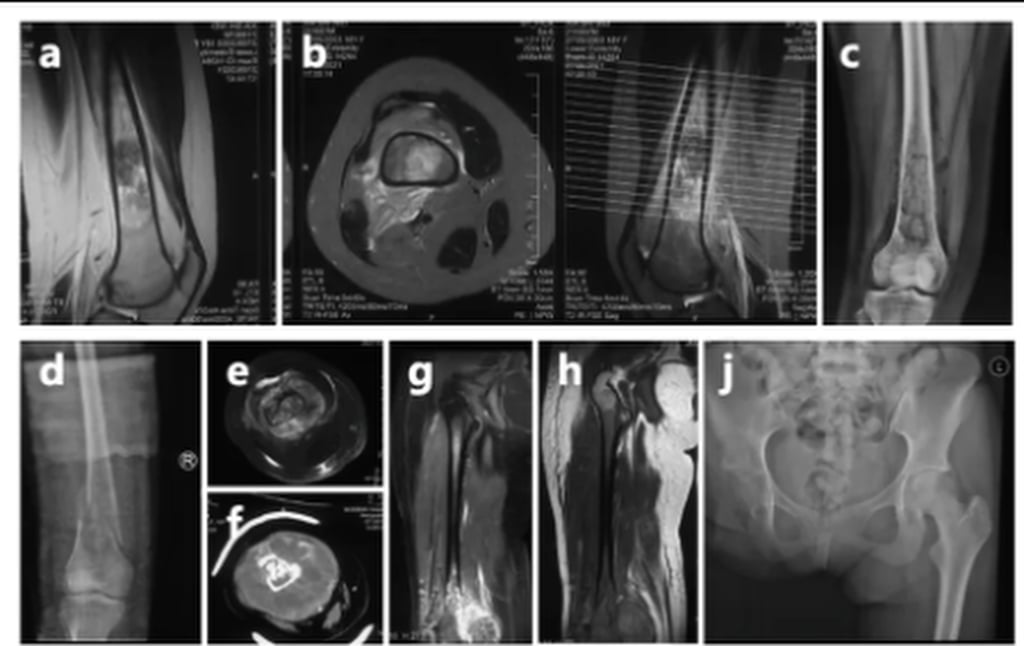

Xia Shiwei, 23, hailing from a village in Anhui province, fainted while taking her college entrance exams in 2021. Despite her condition, she insisted on completing her test and was subsequently diagnosed with bone cancer.

The illness progressed quickly, leading to the amputation of her right leg a year later.